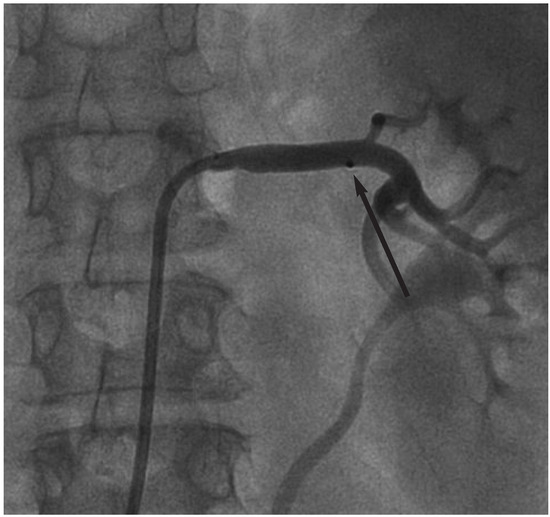

Background: Cardiac resynchronisation therapy (CRT) has become a mainstay in the treatment of patients with severe heart failure mainly due to large clinical trials demonstrating a reduction in morbidity and mortality. The aim of the present study wa...